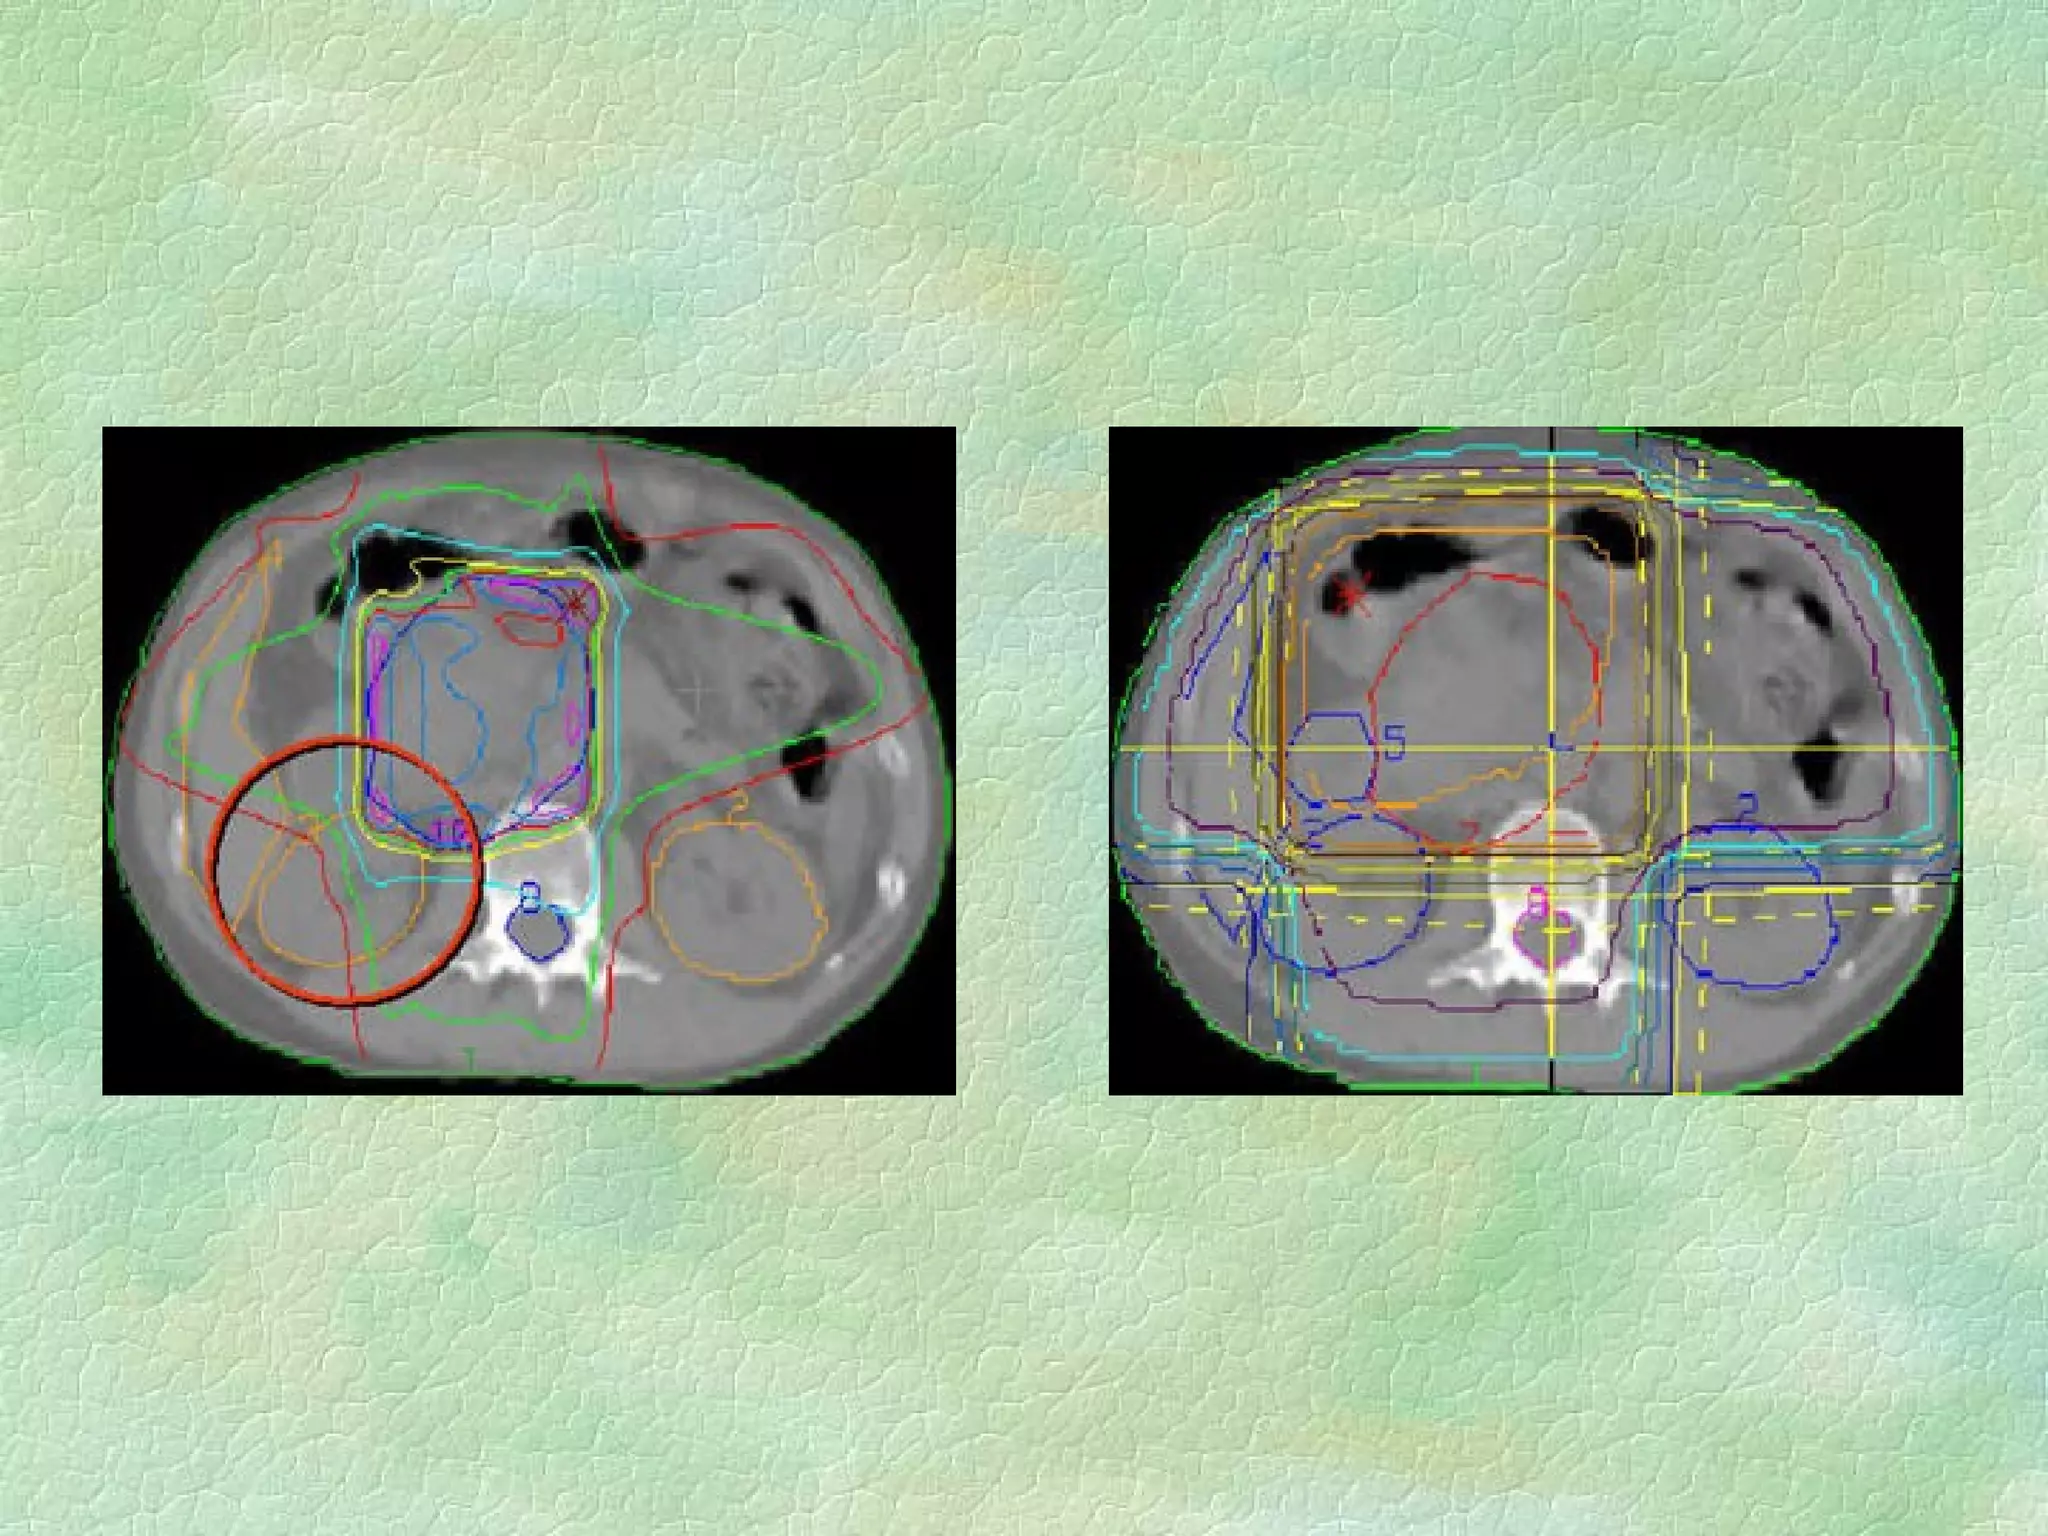

Treatment Planning  Objectives (Goals, Desires, Constraints, etc…) Deliver a uniform dose to PTV Deliver as little dose as possible to OAR Keep integral dose low Reduce number of high dose ‘hot spots’ outside PTV KISS

Treatment Parameters  Degrees of Freedom (with apologies to True Statisticians) Number of treatment beams Individual beam energy Relative beam weighting Shielding Primary beam profile modifiers Patient modifiers (bolus, and other?)

Treatment Optimization Selection of treatment parameters that best conforms to planning objectives Manual: based on experience - time consuming - artform? Automated - forward calculation - compensation Automated - inverse planning - optimization algorithms

Treatment Optimization Selectionof treatment parameters that best conforms to planning objectives Manual: based on experience - time consuming - artform? Automated - forward calculation - compensation Automated - inverse planning - optimization algorithms